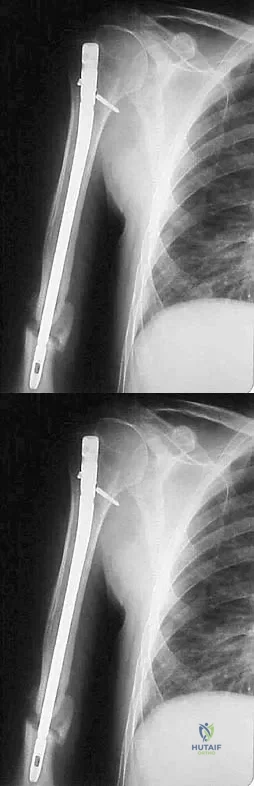

A 31-year-old man sustained a closed injury to his arm in a motor vehicle accident 16 months ago. Treatment of the fracture consisted of intramedullary nailing of the humerus. He now reports pain with minimal activities. Clinical examination and laboratory studies suggest no signs of infection. Radiographs are seen in Figures 12a through 12c. Treatment should now consist of